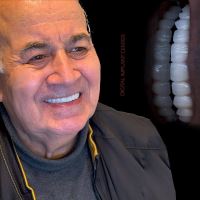

• گالری